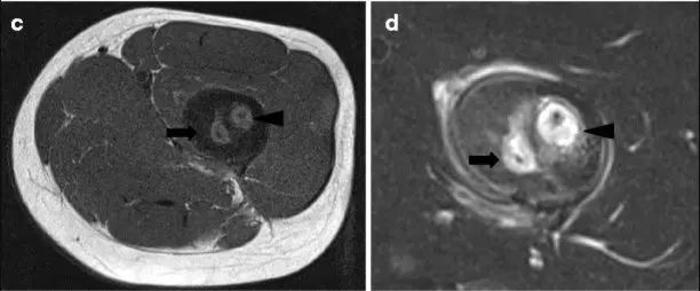

死骨在影像学中的定义与临床有所不同[2]。在影像学上,死骨定义为在透明病变区域内可见的钙化影,与周围骨完全分离,不涉及周围组织及血管状态。在CT及X线片上,可以看到低密度影中间明显大高密度影。仅仅通过CT及X线片一般很难判断是否为实际死骨,可能与骨转移瘤等相混淆。因此,结合增强MR,可以区分坏死组织包裹的死骨是否存在血流,从而判断是否为真正定义上的“死骨”。因此临床上判断死骨时,有必要将MR及CT、X线片等联合运用判断[3]。

(b)CT显影情况,上可见明显死骨形成。图c、d分别为横向T1加权MR及T2加权相MR,可见增强后中间高密度影无明显增强,无明显血流,符合死骨诊断。